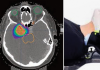

[Á¦ÁÖ, Á¦ÁÖÀÎÀÇ °Ç°º¸°í¼ ¥· °Ç°´ÙÀ̾] (157) °©»ó¼±¾Ï

ÀþÀº ¿¬·ÉÃþ¿¡µµ ÈçÈ÷ ¹ß°ß¹«Áõ»ó Àæ¾Æ Á¶±â Áø´Ü ÇÙ½ÉÁø´Ü ´Ê¾îÁö¸é ÇÕº´Áõ À§Çè·Îº¿ ÀÌ¿ëÇØ ÈäÅÍ ¾øÀÌ ¼ö¼ú ¡¦